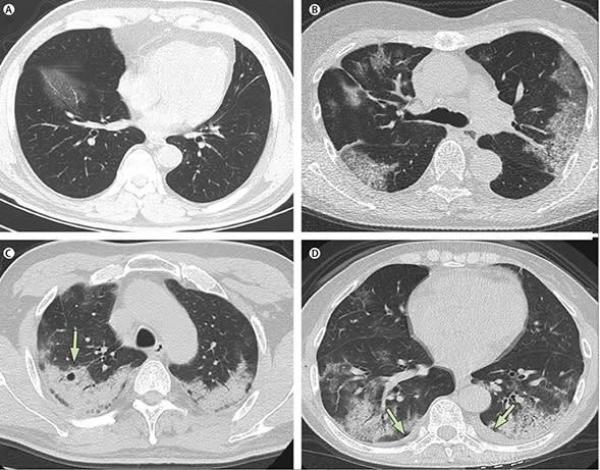

中国大陆疫情大爆发,民众纷纷亮出自己或亲人感染新冠肺炎的白肺照片。 医师 : 患者性命堪忧。(图片来源:微博)

“ 白肺 ” 指的是重症肺炎患者进行 X 光检查时,肺部显影呈现大面积的白色,这表示肺部被严重侵蚀、纤维化,是种极端的肺炎症状,罹患者性命堪忧。

爆料者除了死者家属,也有医护人员,忧心3年前武汉疫情爆发时的典型症状 “ 白肺 ” 再度大量涌现。不少医护人员在微博贴出,在医院拍下的照片,显示不少患者的肺部已经彻底纤维化,相当恐怖。

所谓 “ 白肺 ”,指的是重症肺炎患者进行X光检查时,肺部显影呈现一大片白色,这意味着肺部被严重侵蚀、纤维化,性命堪忧。

“ 白肺 ” 也叫急性呼吸窘迫综合征(ARDS),一般指重症肺炎患者在X光或CT检查下的表现,肺部显影呈一大片的白色状而得名。临床表现为胸闷气短、呼吸不畅,白肺患者的血氧饱和度较低,因此会导致严重缺氧的结果。